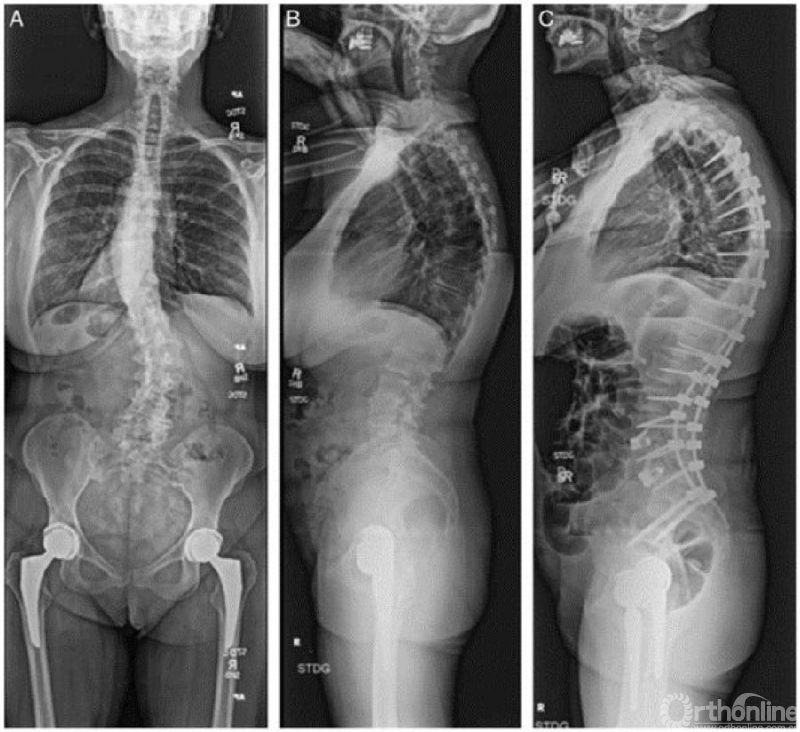

63岁女性,患有症状性退变性脊柱侧凸,术前通过DXA检查、椎体骨折评估(VFA)和机会性CT检查进行综合评估(图3)。桡骨远端T值为-2.5,L1节段CT HU为71。25(OH)-维生素D水平为13。患者术前接受了9个月的特立帕肽治疗,并补充钙剂和维生素D。复查CT显示L1节段HU值提高至110。25(OH)-维生素D提升至32。随后患者接受了T4-骨盆固定融合术。术后继续使用特立帕肽治疗1年,没有发生骨质疏松相关并发症。

图3. A,术前脊柱全长正位片;B,术前脊柱全长侧位片;C,T4-骨盆固定融合术后1年脊柱全长侧位片,没有骨质疏松相关性并发症